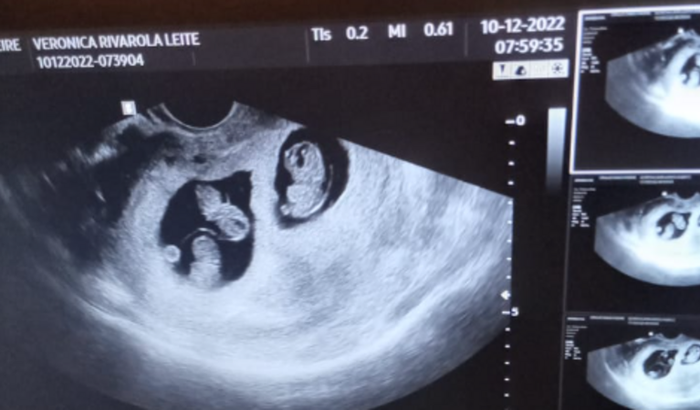

Meu nome é Verônica,tenho 33 anos,moro em Jardim MS e descobri que estou grávida de trigêmeos,já tenho duas filhas do primeiro casamento,estava me relacionando com uma pessoa e depois que eu descobri que estava grávida ele não me procurou mais e não está me ajudando com nada,eu estou desempregada,sempre trabalhei,mais devido a minha gravidez ser de risco,pq tenho pressão alta e diabete gestacional, não posso trabalhar,moro com minha mãe,minha mãe é diarista,e a única renda que temos no momento é a diária dela.Moramos de aluguel e estamos tendo muitas despesas no momento e a diária dela não está dando.Essa gravidez não chega até os 9 meses,e em qualquer momento posso entrar em trabalho de parto por causa das complicações,e ainda falta muita coisa para eles,são 2 meninas e 1 menino.Quem puder me ajudar com qualquer valor que sentir no coração,toda ajuda será bem vinda,e quem não tiver condições me ajuda compartilhando..Muito obrigado a todos